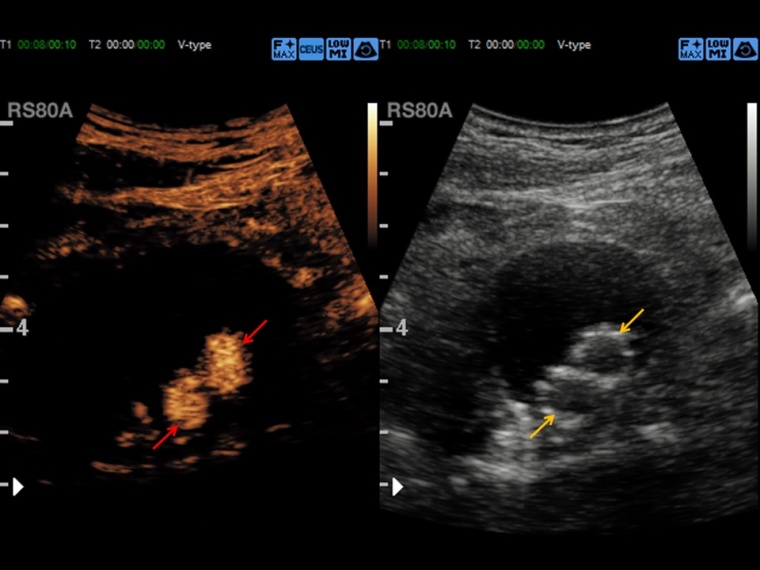

Der kontrastmittelverstärkte Ultraschall, CEUS (Contrast Enhanced Ultrasound) nutzt gasgefüllte Mikrobläschen als Kontrastverstärker zur Erstellung des Sonographiebildes.

Prof. Dr. Dirk-André Clevert: CEUS eignet sich hervorragend für die Beurteilung der Makro- und Mikrozirkulation von Organsystemen, die grundsätzlich für sonografische Fragestellungen untersuchbar sind. Dies umfasst diagnostische Fragestellungen im Bereich der Beurteilung von Läsionen und Raumforderungen von parenchymatösen Oberbauchorganen, aber auch die vaskuläre Diagnostik von Gefäßen, z. B. bei Patienten nach endovaskulärer Aortenreparatur. Ein Großteil der Diagnostik in unserer Abteilung behandelt die Abklärung von unklaren Leberraumforderungen oder komplexer Nierenzysten.

Clevert: CEUS ist eine schnelle, leicht durchzuführende und kosteneffektive Methode zur Diagnostik von abklärungsbedürftigen Befunden. Der Vorteil der Methode liegt in der schnellen Verfügbarkeit und der Dynamik der Untersuchungsmethode. Können in alternativen radiologischen Schnittbildgebungen beispielsweise nur einzelne Kontrastphasen akquiriert werden, so ist es mit dem CEUS möglich, die dynamische Perfusion von Gewebe oder von Gefäßen über mehrere Minuten zu beobachten, und so differenzierte Aussagen zu treffen. Ein weiterer großer Vorteil der Methode besteht darin, dass das verwendete Kontrastmittel unabhängig von der Nieren- und Schilddrüsenfunktion verwendet werden kann und somit der CEUS auch bei Patienten mit Niereninsuffizienz bzw. mit hyperthyreoter Stoffwechsellage zum Einsatz kommen kann.